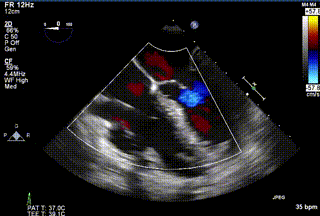

三例患者入院后,葛均波院士團隊周達新教授、潘文志教授、張源博士、陳莎莎博士及心超室的潘翠珍教授、李偉教授對患者的情況進行詳細評估和討論,最終決定為三例患者選擇LuX-Valve Plus40mm、50mm和50mm型號的瓣膜進行手術治療。手術后即刻拔除氣管插管,術后患者三尖瓣反流癥狀得到顯著改善,復查心超結果顯示人工三尖瓣瓣膜支架固定穩定,瓣葉關閉形態未見異常,未見明顯反流。